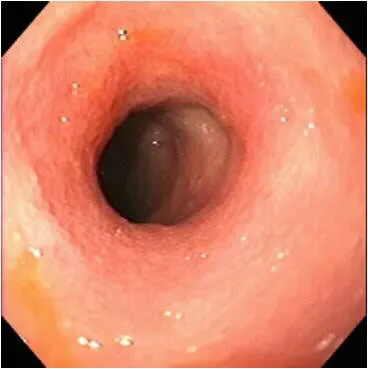

The best biopsies are obtained by directing the instrument at a 90° angle (perpendicular) to the mucosal surface at flexure locations (A). (Note the numerous white spots along the mucosa, which are areas of light reflection, not lymphangiectasia.) Flexure sites facilitate targeted, deep mucosal tissue purchases while reducing the tendency of the forceps cups to slide along the superficial mucosa. Tissue biopsies procured at nonflexure sites will require directing the endoscope tip (and biopsy forceps) obliquely toward the mucosa.

If the patient is large, use of a “long-distance” biopsy technique may be warranted. The biopsy forceps is passed as far as possible down the lumen until resistance is met. Usually the forceps cups are beyond the operator’s view distally (B). Once resistance is encountered, the forceps are retracted slightly (to open up the jaws) then readvanced firmly against the mucosa where a tissue specimen is obtained (C).

The disadvantages of this technique are its “blinded” approach and the tendency to biopsy repeatedly in the same site. Mucosal perforation is a potential but extremely unlikely complication of this procedure. The technique is often used and quite successful.